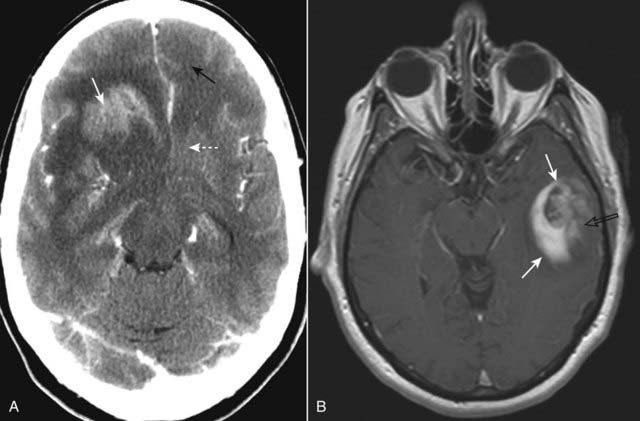

imageRecognizing glioblastoma multiforme

image As the most aggressive of tumors, glioblastoma multiforme frequently demonstrates necrosis within the tumor.

image The tumor infiltrates the surrounding brain tissue, frequently crossing the white matter tracts of the corpus callosum to the opposite cerebral hemisphere producing a pattern called a butterfly glioma.

image It tends to produce considerable vasogenic edema and mass effect and enhances with contrast, at least in part (Fig. 25-27).

Figure 25-27 Glioblastoma multiforme, CT and MRI, two different patients.

A, In this contrast-enhanced CT, the tumor enhances (solid white arrow), produces considerable vasogenic edema (dotted white arrow), and infiltrates the surrounding brain tissue. There is either edema or tumor that has crossed over to the left frontal lobe (solid black arrow). B, Axial T1-weighted postgadolinium image in another patient demonstrates an enhancing mass in the left temporal lobe (solid white arrows). The internal enhancement of the mass is somewhat heterogeneous (open black arrow), which implies intratumoral necrosis or cystic change.

Metastases

image Solitary intraaxial masses are about evenly split between solitary metastases and primary brain tumors. About 40% of all intracranial neoplasms are metastases. Lung, breast, and melanoma are the most common primary malignancies to produce brain metastases.

imageRecognizing metastases to the brain

image Metastases to the brain are frequently well-defined, round masses near the gray-white junction.

image They are usually multiple, but can be solitary.

image They are typically hypodense or isodense on nonenhanced CT.

image With intravenous contrast, they can enhance, sometimes with a pattern of ring-enhancement.

image Most evoke some vasogenic edema, frequently out of proportion to the size of the mass (Fig. 25-28).

Figure 25-28 Metastases, contrast-enhanced CT.

About 40% of all intracranial neoplasms are metastases. They typically produce well-defined, round masses near the gray-white junction and are usually multiple. With intravenous contrast, they can enhance, sometimes demonstrating ring enhancement (solid white arrows). Lung, breast, and melanoma are the most common primary malignancies to produce brain metastases. This patient had lung cancer.